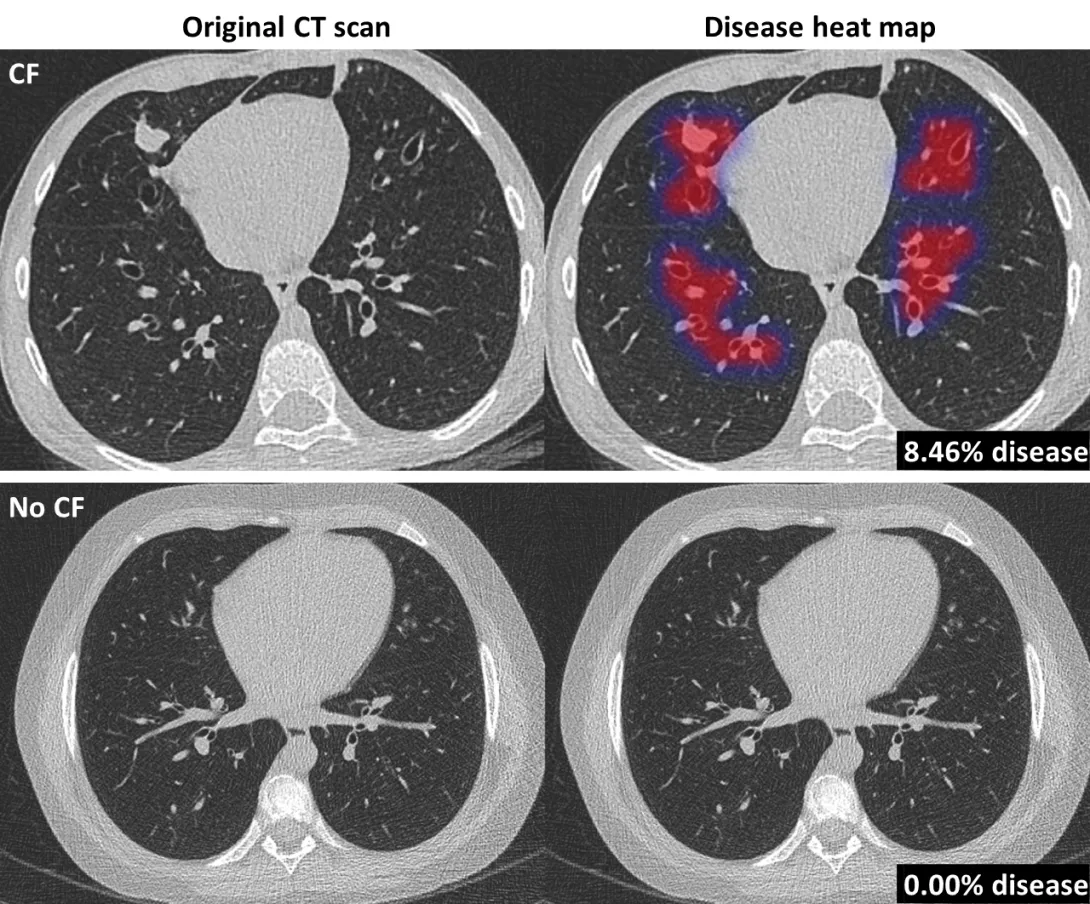

Nijmegen-based AI software company, Thirona has developed an AI algorithm to detect and quantify lung abnormalities related to cystic fibrosis (CF).

PRAGMA-AI aims to process faster and automated analysis of CT scans of patients with the condition, delivering an assessment in several seconds.

PRAGMA-CF is a quantitative method for the assessment of CF lung disease on CT scans and lung irregularities related to CF, such as abnormal airways and collapsed lung tissue. These quantifications are critical in determining the status of the patient and treatment paths but are not feasibly performed by humans in clinical care.

The method also takes up to several hours per patient and requires specialised data analysts. Thirona has now automated this method to analyse CT scans of CF patients in several seconds, without human interference.

The new AI-based algorithm PRAGMA-AI aims to enable large-scale usage in clinical trials and clinical care for better diagnostics, patient monitoring, and treatment planning.

LungQ PRAGMA-AI has been validated on a large number of scans of CF patients, showing high diagnostic performance comparable to trained human analysts.